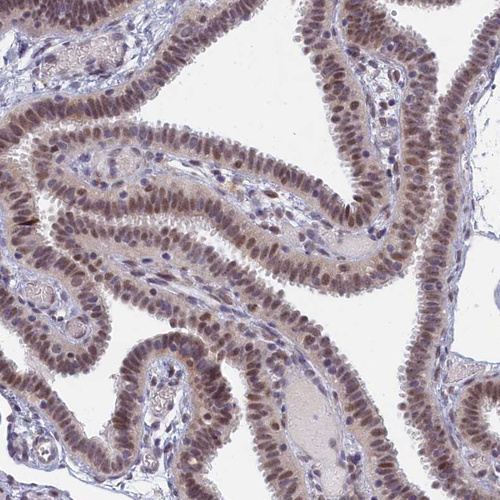

Immunohistochemical staining of human fallopian tube shows moderate nuclear positivity in glandular cells with weak cytoplasmic positivity.